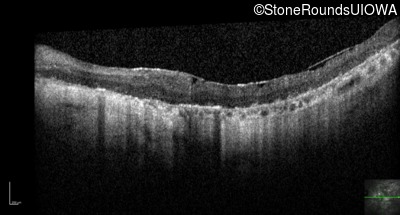

Optical Coherence Tomography - Right - Hand Motion 1' sc

Exemplar / OCT Stack

OCT Stack